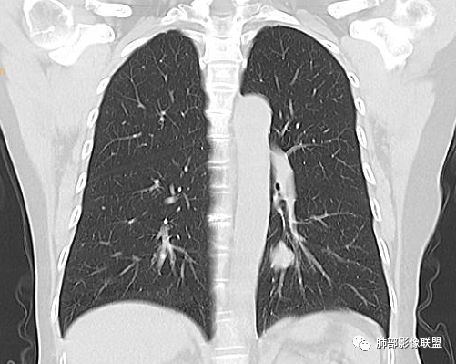

Shelia:隆突下没看到肿大淋巴结呀南边:那就是支气管应该是堵了。图少了一点

wonderful:纵膈有吗徐超:隆突下没有肿大淋巴结。思路没问题,主要还是支气管的关系。还有CT值,有测量值最好。强化不同疾病范围不同,虽然有叠加Coke with ice:这个病灶好像有浅分叶,是否有鉴别意义呢南边:可能绕过去了。浅分叶没什么价值,深分叶有Forever:动脉期强化不太均匀 而且ct值不高我觉得有提示意义

而且这例没看见肿大淋巴结

M-Imaging :淋巴结肿大的也不明显。下次看见,还是考虑良性

7.病灶的形态及强化程度都不能排除小细胞癌及大细胞癌,纵隔尤其是隆凸下未见增大淋巴结似乎不符合小细胞癌等的生物学行为。

1.图片未能提供病灶与支气管的确切关系,支气管截断有助于大细胞癌或腺癌的判断,管腔狭窄有助于小细胞癌的判断。

2.CT扫描到手术病病理相隔多久?影像并未显示隆凸下增大的淋巴结。

3.图像显示的结节影,它一定是该患者小细胞癌的发祥地吗?外围存在隐匿病灶吗?可惜我们没有更加全面的资料,殊为憾事!